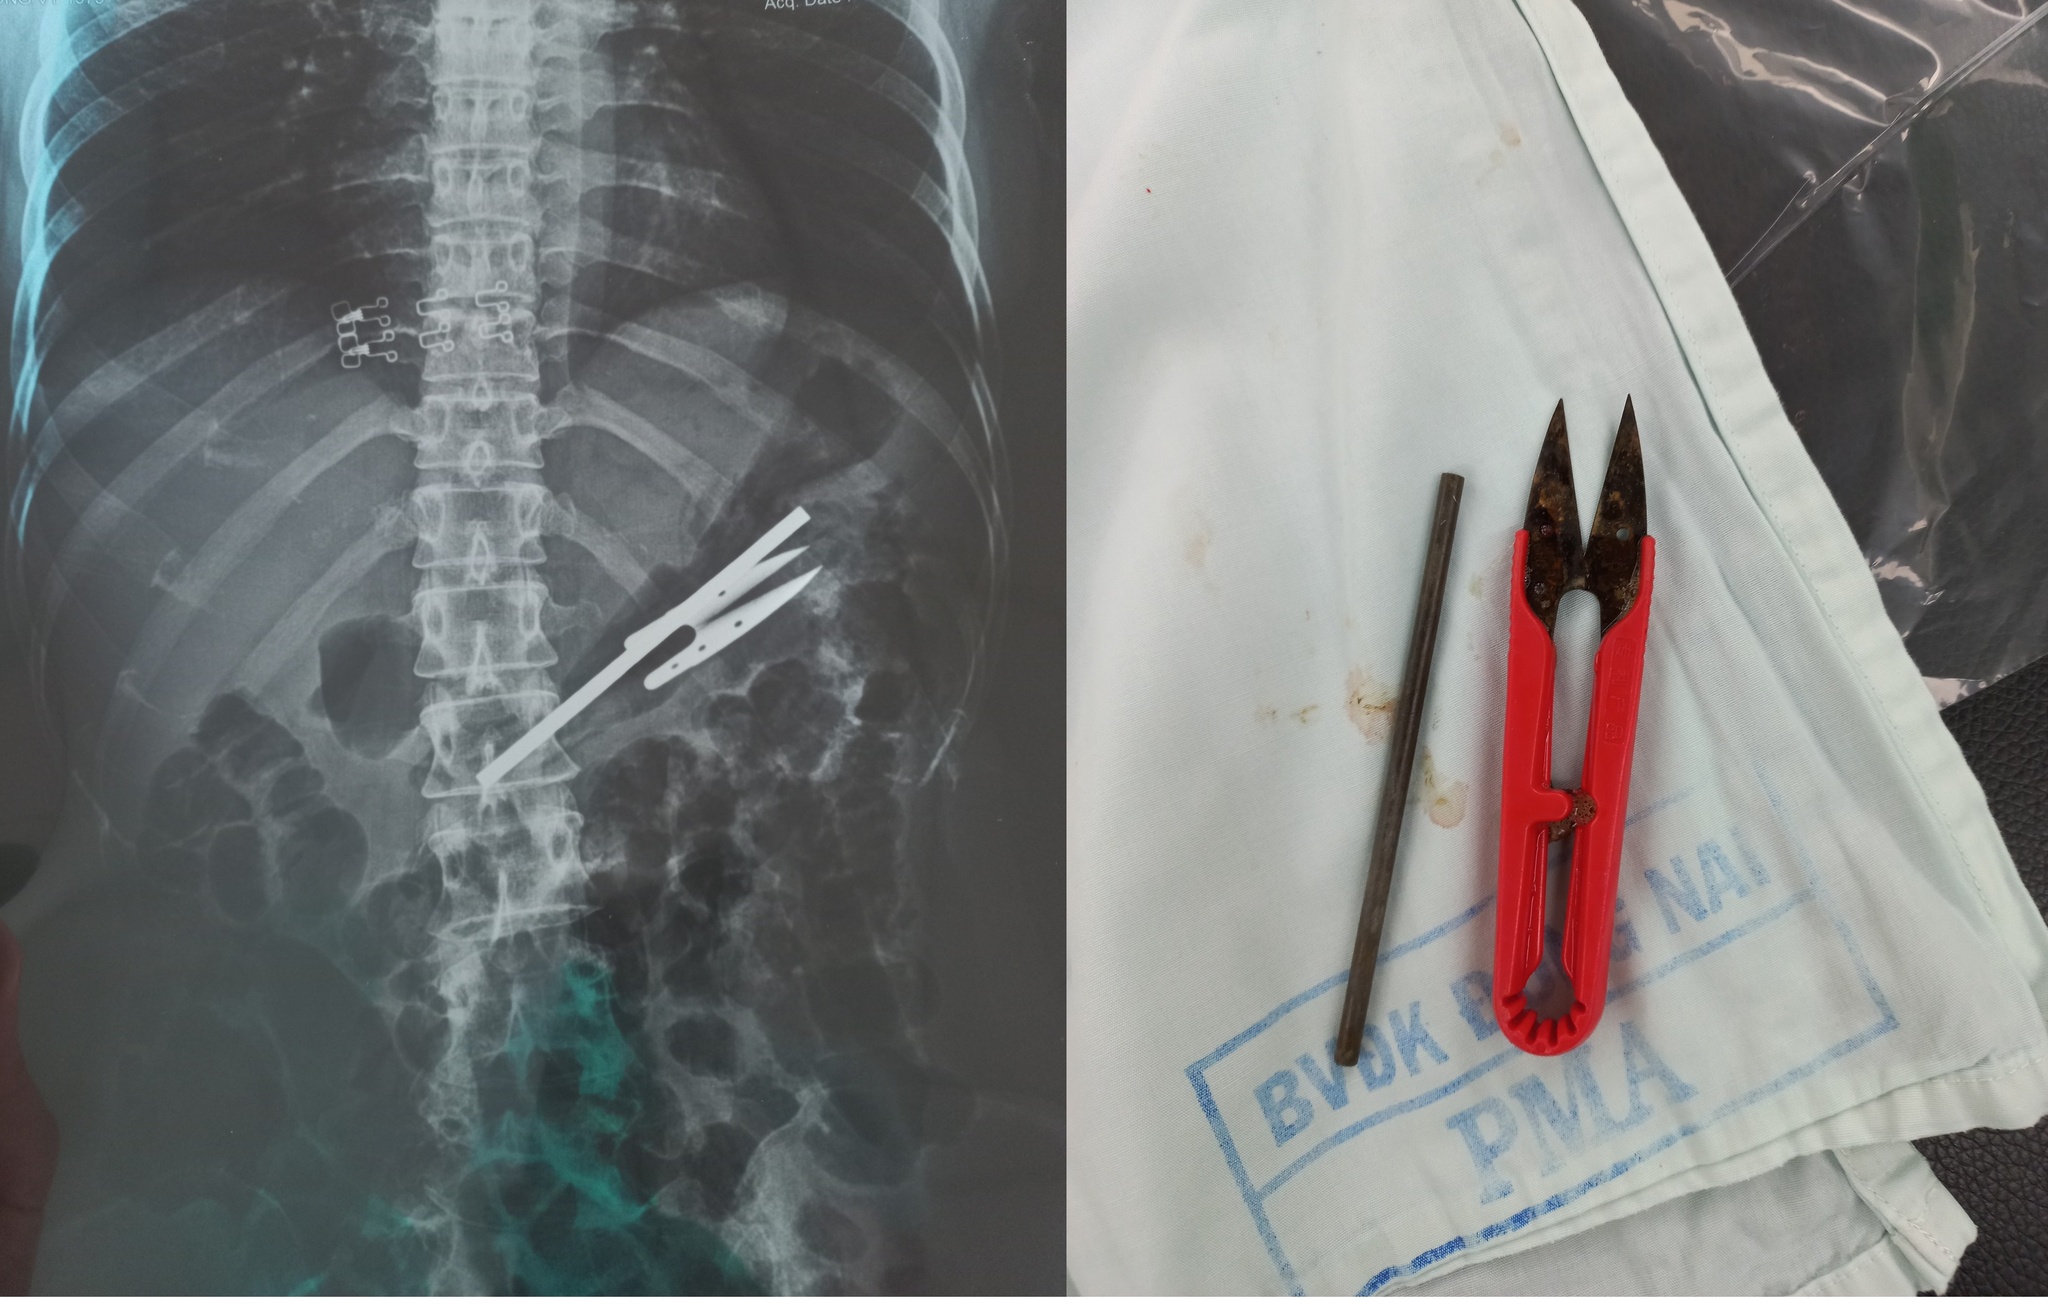

Qua chụp X-quang, phát hiện trong dạ dày bệnh nhân có 1 cây kéo cắt chỉ và 1 thanh kim loại. Các bác sĩ đã mất 1 giờ 30 phút nội soi mới gắp được các dị vật ra ngoài.

2 dị vật trong dạ dày bệnh nhân được gắp ra ngoài ẢNH BỆNH VIỆN CUNG CẤP |

Trước đó, bệnh nhân N.T.T.V (43 tuổi, ngụ P.Trảng Dài, TP.Biên Hòa; có dấu hiệu tâm thần) nhập viện trong tình trạng đau bụng nhiều, nôn ói. Qua chụp X-quang, các bác sĩ phát hiện trong dạ dày bệnh nhân có 2 dị vật.

Bác sĩ, Huỳnh Phúc Hưng, Trưởng khoa Tiêu Hóa (Bệnh viện đa khoa Đồng Nai), người trực tiếp thực hiện ca nội soi cho biết sau 1 giờ 30 phút đã gắp thành công được 2 dị vật ra ngoài. Đó là một cây kéo cắt chỉ và 1 thanh kim loại (cả 2 dài khoảng 10 cm).